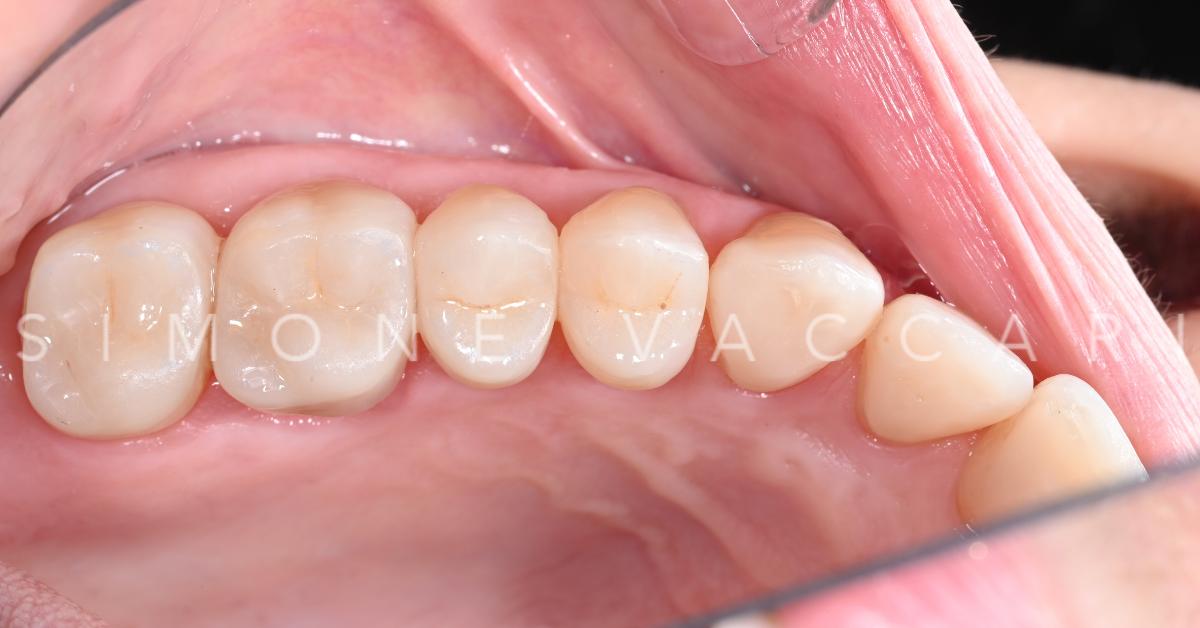

I danni del bruxismo prima del trattamento

Dopo il trattamento